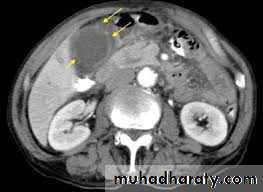

• CT is the imaging investigation of choice for the diagnosis of acute pancreatitis.

CT signs of acute pancreatitis include

• Diffuse or focal pancreatic swelling

• Indistinct pancreatic margins

• Thickening of surrounding fascial planes.

• CT performed during infusion of contrast material can differentiate necrotic non-enhancing tissue from viable enhancing tissue; the presence of pancreatic necrosis is associated with a significantly increased mortality.

• Complications of pancreatitis, such as phlegmon, abscess and pseudocyst, splenic vein thrombosis, arterial erosion and pseudoaneurysm are well shown on CT.